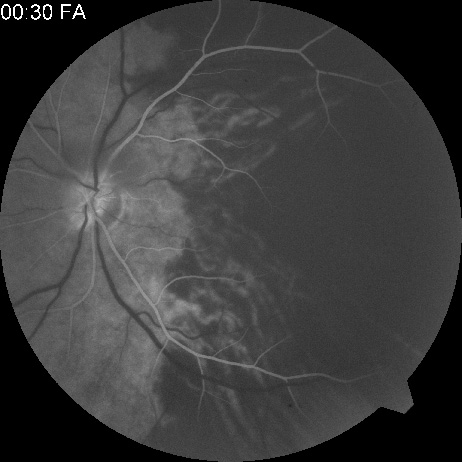

Ophthalmic artery obstruction is characterized by an initial opacification of the entire retina in a manner similar to that of central retinal artery obstruction (Fig. 4A). The cherry-red spot may or may not be present, however.119 The difference between an ophthalmic artery obstruction and central retinal artery obstruction is that in an ophthalmic artery obstruction, with time, optic atrophy develops, as does varying amounts of pigmentation due to the lack of perfusion of the retinal pigment epithelium (see Fig. 4D). This pigment is generally diffusely scattered throughout the posterior pole but it may also be seen in greater amounts in the periphery.

Intravenous fluorescein angiography generally shows moderate to marked abnormalities in the filling of the choroid, in addition to a delay in filling or even nonfilling of retinal vessels (see Fig. 4B and 4C). Staining of the retinal pigment epithelium can also be seen; this staining either can occur locally in the macular area or it can be diffuse.119 The electroretinogram shows abnormalities of both a- and b-waves, reflecting ischemia to both the inner and outer retina. Almost all reported patients have had an initial visual acuity of no light perception; virtually no patients can be expected to have a final visual acuity better than that.119 An acuity of no light perception is a clue to the presence of an ophthalmic artery obstruction. Because relatively few patients with central retinal artery obstruction have an initial visual acuity of no light perception, no light perception usually suggests the likelihood of some obstruction of the choroidal circulation.14